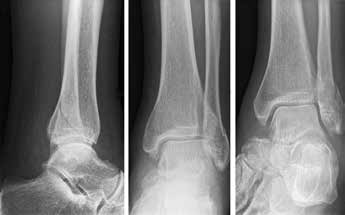

Arthrose stellt weltweit die häufigste Gelenkerkrankung dar und hat damit einen wesentlichen sozioökomischen Einfluss 1. Während 15 % der weltweiten erwachsenen Bevölkerung von Arthrose betroffen sind 2, leiden lediglich 1 % der Bevölkerung 3 bzw. 4,4 % der Arthrosepatienten 4 an einer Arthrose des oberen Sprunggelenks (OSG). Circa 80 % der Arthrosen des OSG sind ursächlich als posttraumatisch einzustufen, nur 9 % gelten als primäre Arthrosen. Dies unterscheidet die Arthrose des OSG von Coxarthrose (58 % primär) und Gonarthrose (67 % primär). 13 % treten im Rahmen systemischer Erkrankungen wie rheumatoider Arthritis, Hämochromatose, Hämophilie oder Osteonekrose auf 5 6. Die posttraumatische Arthrose des OSG wird besonders nach in Achsabweichung verheilten Frakturen (Pilon-tibiale-Frakturen, Weber-A‑, ‑B- und ‑C-Frakturen; Abb. 1a), Bandinstabilitäten des lateralen und medialen Bandapparates des OSG (Lig. fibulotalare anterius, Lig. fibulocalcaneare, Lig. fibulotibiale posterius etc.), nach rezidivierenden ligamentären Verletzungen sowie nach Gelenkverletzungen mit Knorpelschaden, „flake fractures“ oder „bone bruise“ beobachtet 7. Daher ist bei den vergleichsweise häufigen Weber-B- und ‑C-Frakturen die osteosynthetische Versorgung mittels Drittelrohrplatte und Zugschraube (Abb. 1b) sowie ggf. Syndesmosennaht mit Implantation einer Stellschraube mit millimetergenauer Reposition essentiell, um langfristig die Funktionsfähigkeit des OSG aufrechtzuerhalten und eine frühzeitige posttraumatische Arthrose zu verhindern 8.